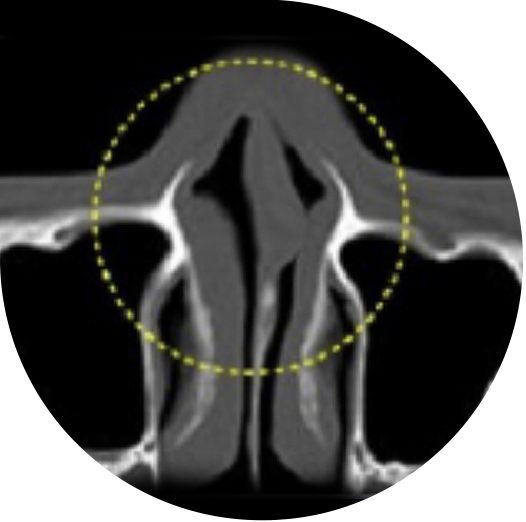

曲がった鼻

曲がった鼻とは、鼻筋から鼻先まで続くラインがC字型やS字型に 曲がって見える鼻のことです。

湾曲の程度に応じて、鼻筋の非対称性を矯正し、軟骨移植を行うことで、機能面と美容面の両方を改善します。

曲がった鼻の手術ノウハウ

曲がった鼻の場合、90%以上が鼻中隔湾曲症を伴っています。

ラボムの曲がった鼻整形は、鼻筋の非対称性を矯正し、弱くなった部位の

機能的補完のために軟骨移植を行います。

左右の鼻骨が対称になるように鼻骨を骨切りし、鼻先軟骨の微細な組織によって対称になるように仕上げます。

鼻中隔湾曲症 C型の矯正範囲

鼻中隔湾曲症 S型の矯正範囲